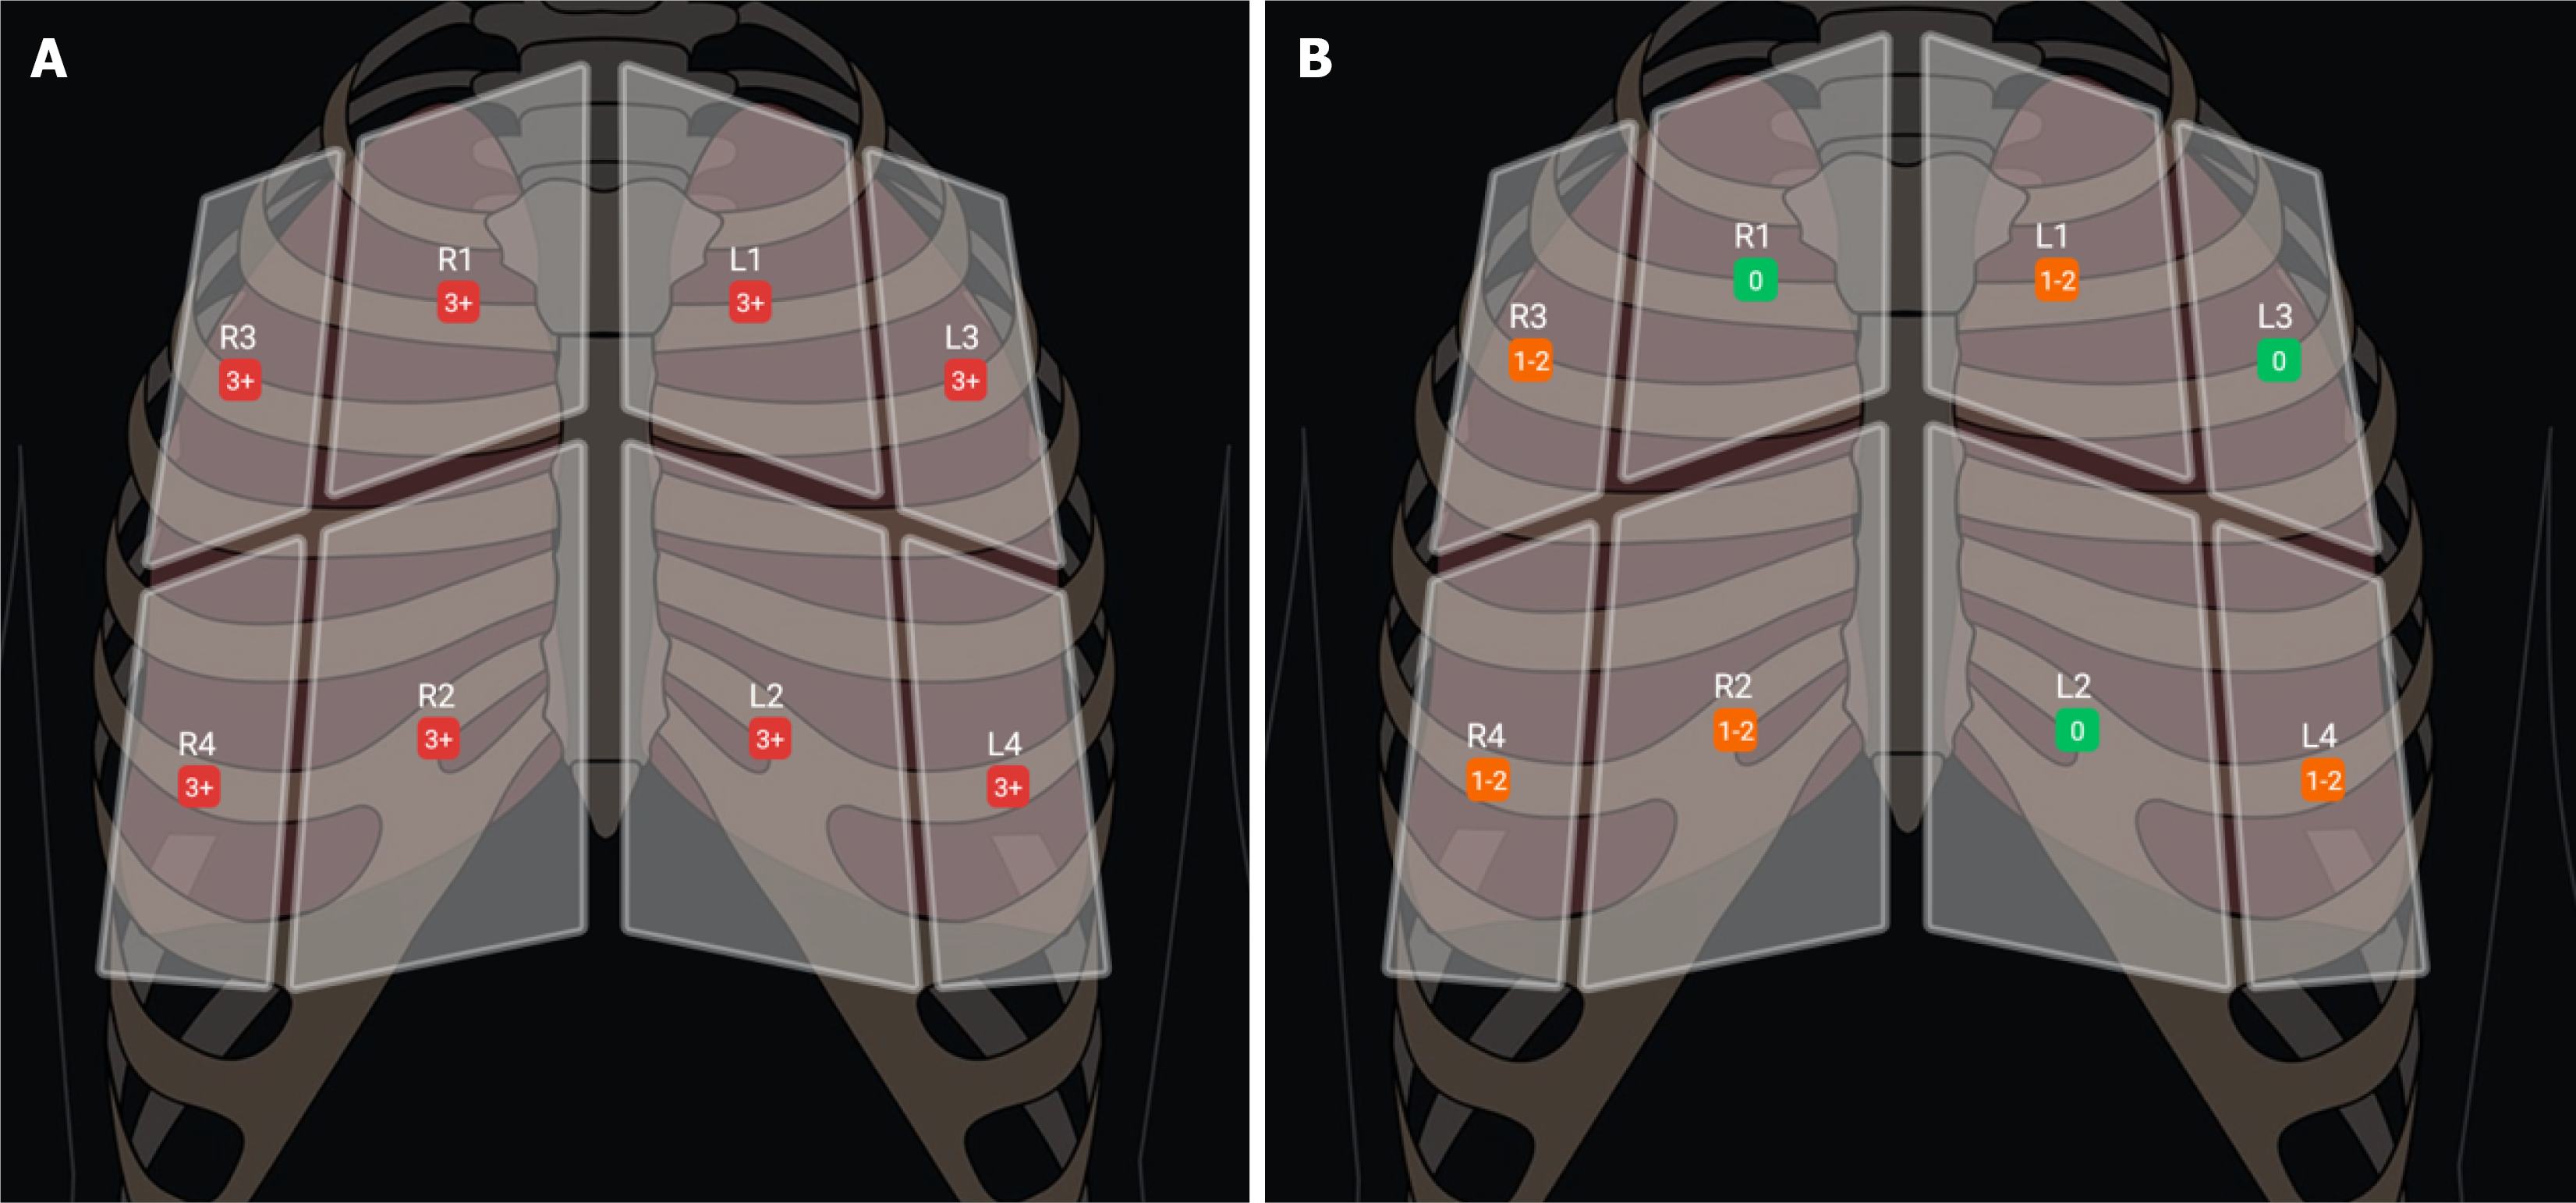

Several studies indicated that the traditional 28-zone LUS is probably not necessary in routine clinical practice[24-27]. Torino and colleagues reanalyzed data from 303 of the original 392 patients in Zoccali's observational hemodialysis cohort and found that a simplified 8-zone LUS strongly correlated with the full 28-zone method, showing a correlation coefficient of ρ = 0.93 (P < 0.001) and a good level of agreement, with a concordance of k = 0.79[24]. At a minimum, a 4-zone LUS assessing the upper anterior and lower lateral regions of bilateral lungs is sufficient to guide diuresis in heart failure or ultrafiltration in patients undergoing hemodialysis[11]. In our clinical practice, we routinely perform an 8-zone LUS examination, as described previously. Some ultrasound devices offer automated B-line quantification that produces a zonal summary, as illustrated in Figure 3. This feature facilitates standardized documentation and helps track changes in pulmonary congestion over time by allowing easy comparison with previous studies.

Figure 3

Figure 3 Eight-zone B-line summaries obtained using a handheld ultrasound device (Philips Lumify®) in a patient with end-stage kidney disease. A: Pulmonary edema following a missed hemodialysis session, with three or more B-lines counted by the machine in each lung zone; B: Marked improvement after 35 liters of ultrafiltration, now showing only one to two B-lines per zone, though there remains potential for further improvement with additional fluid removal.